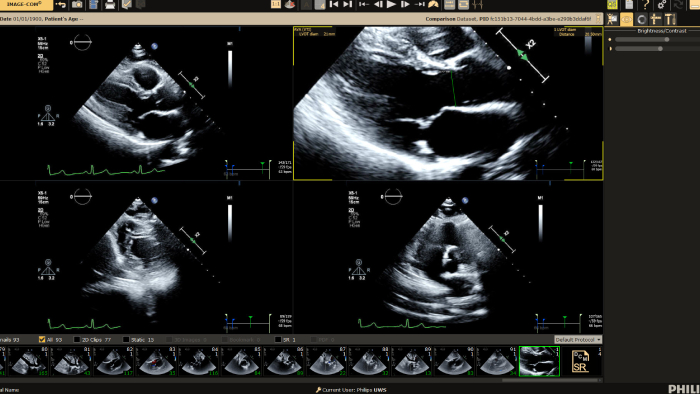

You can still access recordings of 4 full days of hands-on workshops about best practices in multimodality cardiac imaging with expert teams. See first-time-right imaging for cardiac care, including valvular and related diseases, cardiomyopathies, and intracardiac masses and cardiac tumors. Sign up to receive access to these on demand sessions and other news about Philips and cardiac care.

Allow for greater efficiency in viewing, analysis and reporting by giving care teams the flexibility to adopt different workflows based on their current and future needs.

Provide a single point of access to patient’s cardiovascular diagnostic information and multi-modality images at excellent diagnostic quality, including prior exams, as well as findings, measurements, and reports.